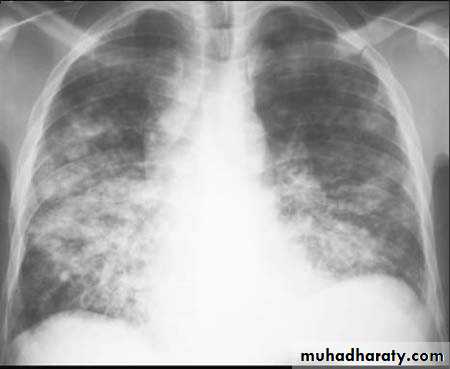

4. Miliary tuberculosis is uncommon but carries a poor prognosis. It represents haematogenous dissemination of an uncontrolled tuberculous infection. It is seen both in primary and post-primary tuberculosis. Although implants are seen throughout the body, the lungs are usually the easiest location to the image. Miliary deposits appear as 1-3 mm diameter nodules . are uniform in size and uniformly distributed